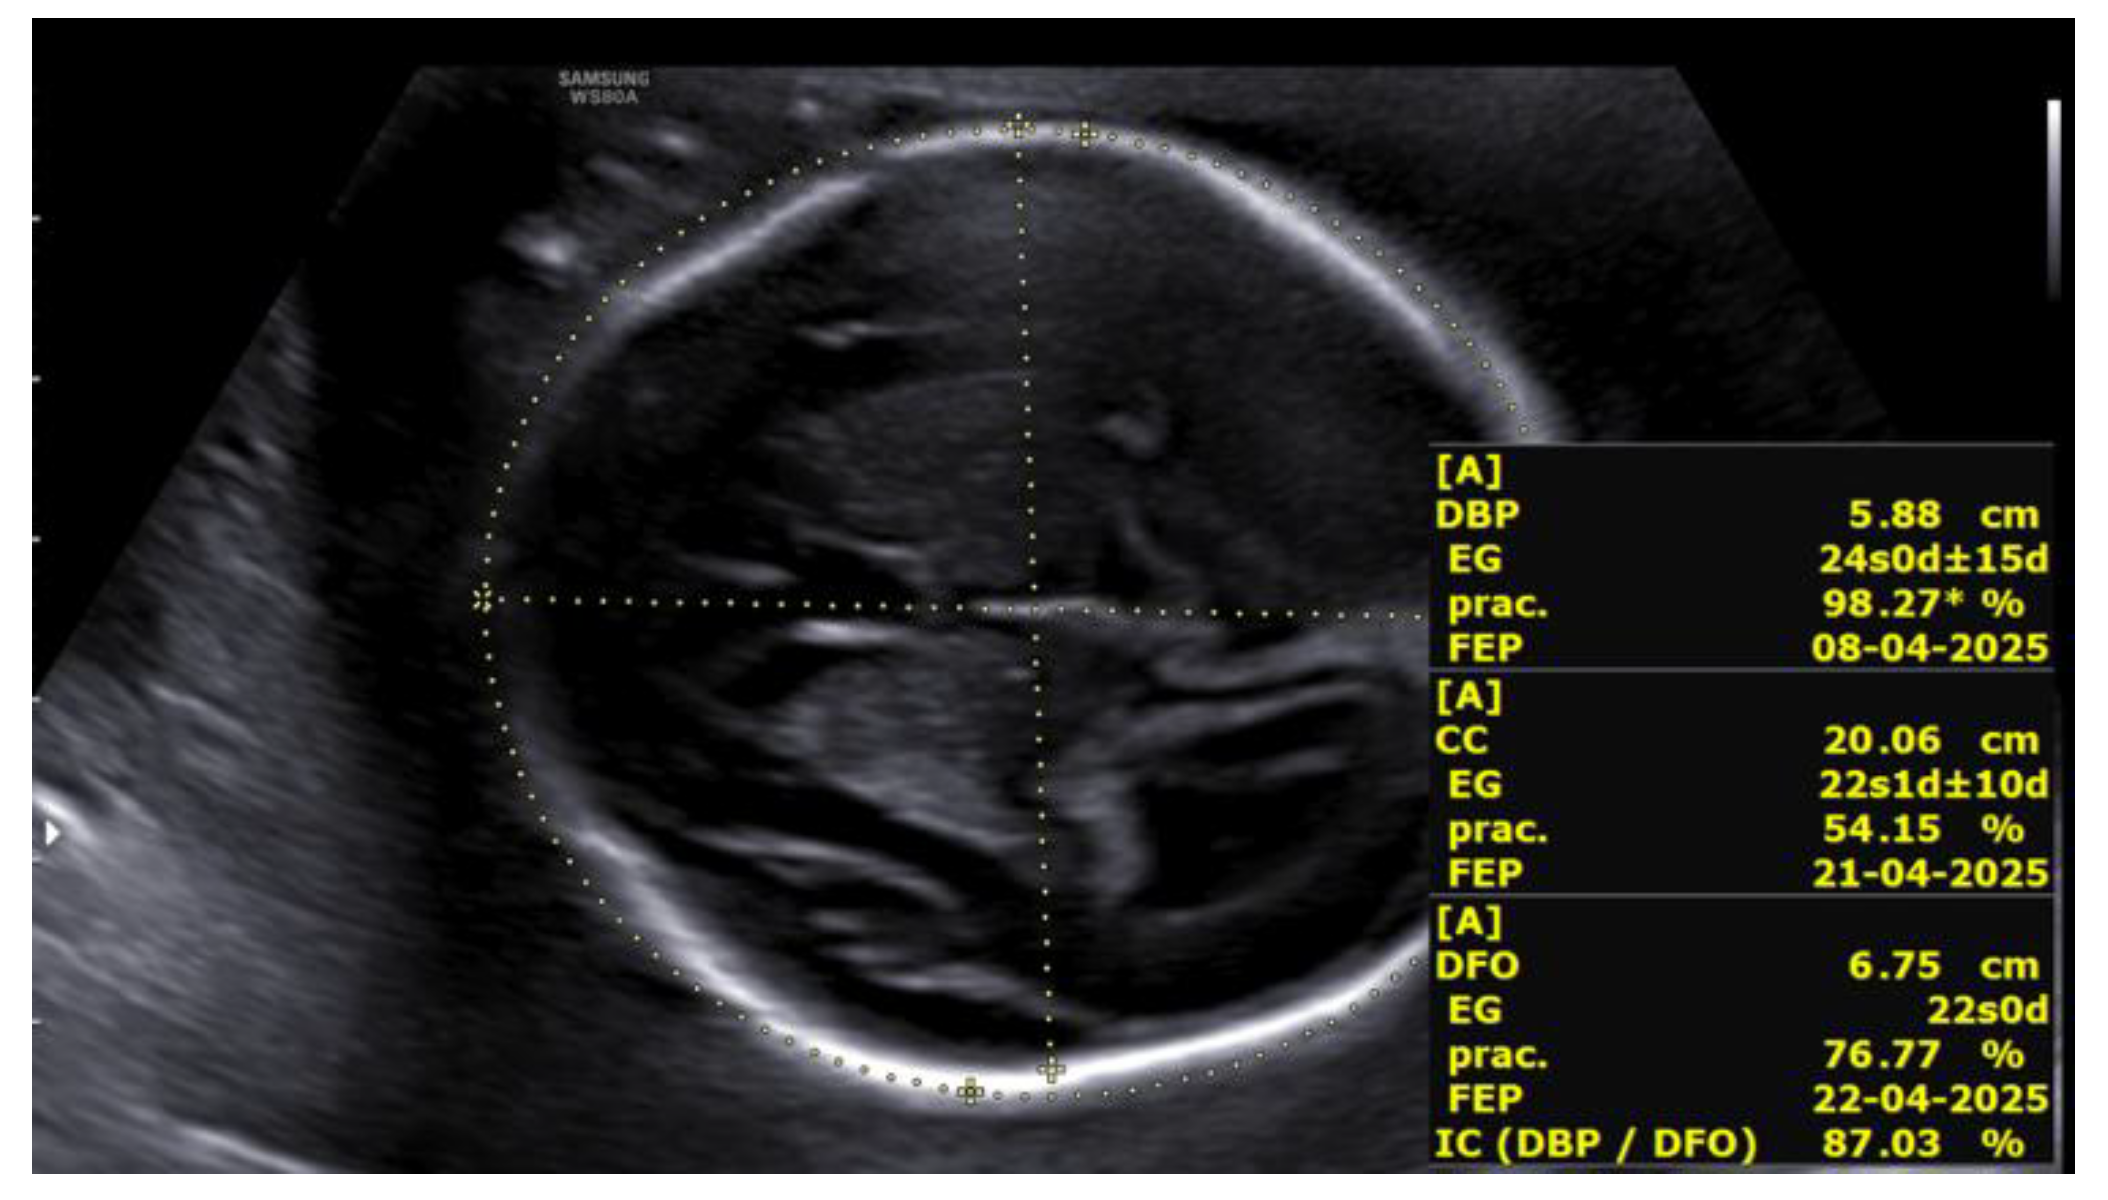

At 23+5 weeks, the first fetus, with positive cardiac activity and fetal movements and located in the left hemiabdomen in cephalic presentation, showed biometry consistent with 22+5 weeks, a three-vessel umbilical cord, and normal umbilical artery Doppler. Middle cerebral artery Doppler indicated absence of fetal anemia. Intracranial evaluation revealed normal lateral ventricles and supratentorial structures, with a cephalic index of 87%, compatible with brachycephaly (Figure 3).

Figure 3. Cephalic index >85% (brachycephaly) in the first fetus at 23+5 weeks.